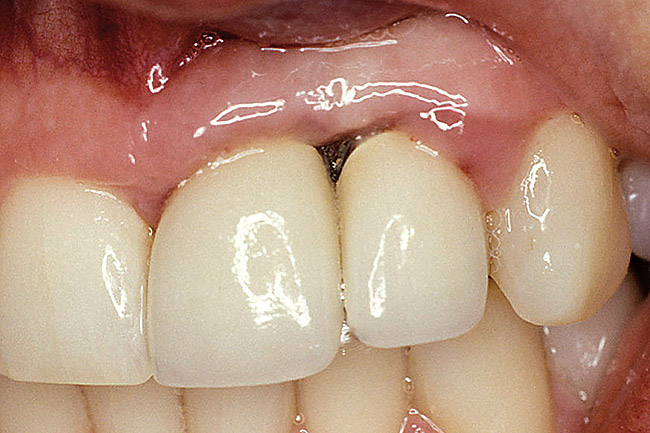

Figure 25  A patient presented with a significant ridge defect, but with surgeon-placed adjacent implants in the lateral and cuspid positions.

Figure 25

Figure 26  A pediculated connective-tissue graft was used to augment the soft-tissue height.

Figure 26

Figure 27  The lateral incisor implant was put to sleep and the cuspid implant uncovered.

Figure 27

Figure 28  The final restoration exhibits a cantilevered incisor off of a canine implant.

Figure 28